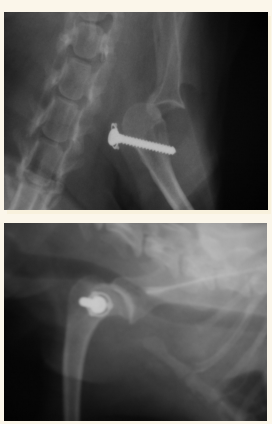

Cadera

En general se hacen proyecciones:

- Ventro-dorsal: Extender extermidades y traccionar, sin rotación axial, paralelas a la mesa, buscamos que la rotula se superponga con el surco troclear. Posicion de rana si es una fractura pelvica

- Latero-Lateral: Esponja de gomaespuma entre rodillas, estirar extermidades posteriores a caudal

Problemas mas comunes:

- Displasia

- Luxación sacroilíaca

- Luxación coxo-femoral

- Fracturas articulares

- Necrosis avascular de la cabeza femoral

- Fracturas pélvicas (generalmente múltiples y afectan a tejido blanco coetáneo)

- Necrosis avascular de la cabeza femoral (Enf. de Legg-Calvé-Perthes) IMPORTANTE, LO SUELE PREGUNTAR

Luxación Coxo-femoral

- Por traumatismo, a veces leve si existe Displasia. Suele aparecer con fracturas de pelvis, uni o bilateral

- Normalmente cráneo-dorsal, aunque puede ser dorsal, ventral, caudal (rara) o intrapélvica

- Mejor 2 proyecciones pero en VD se ve mejor (ilion desplazado, mayor tamaño articular, perdida de contorno liso)

- Tambien hay luxacion sacro iliaca.

- Hay que ver la direccion de la luxacion. La mas frecuente es craneo-dorsal pero hay mas.

Necrosis avascular CF o Enfermedad de Legg-Calve-Perthes LO SUELE PREGUNTAR

- En cachorros de razas pequeñas

- Por defecto de vascularizacion de la cabeza y cuello femorales, cojera sobre todo en frio.

- Areas de radiolucidez en cabeza de fémur

- Deformación cabeza y cuello, se pierde siluheta de la cabeza del femur

- Muy dolorosa generalmente y con atrofia muscular

- Exéresis de CCF (cabeza y cuello femoral)